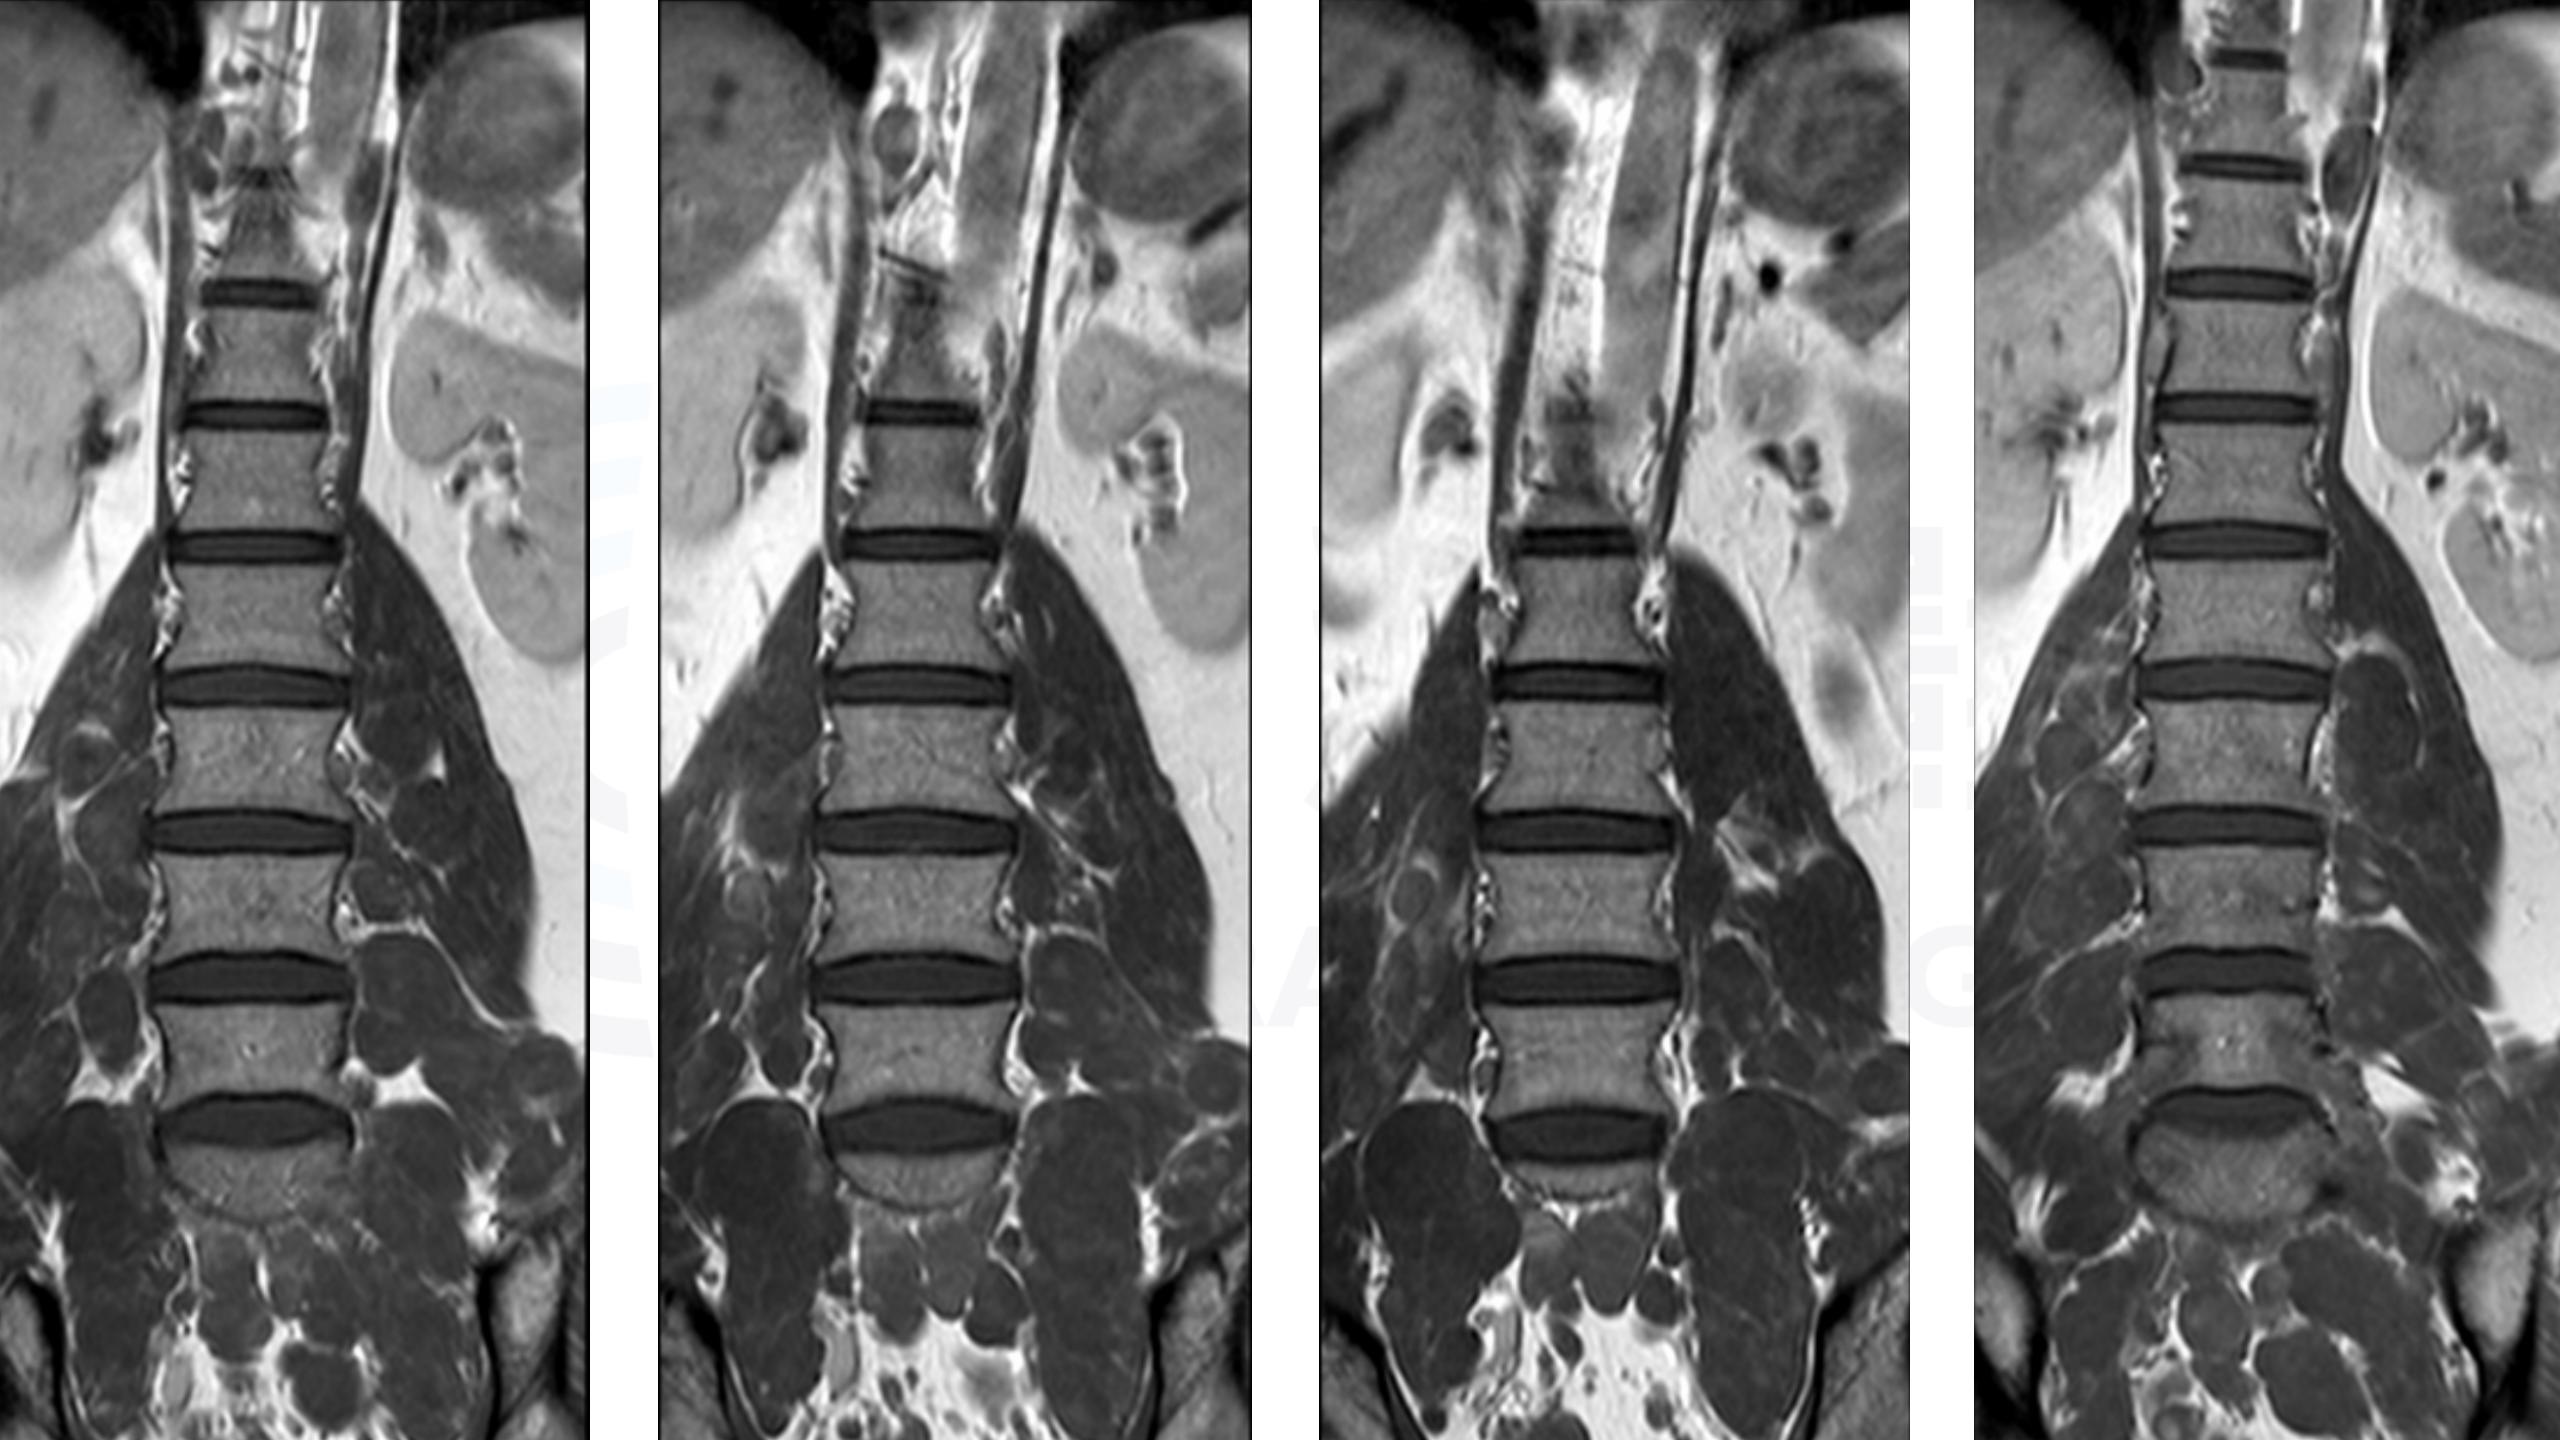

神经纤维瘤病(NF1)